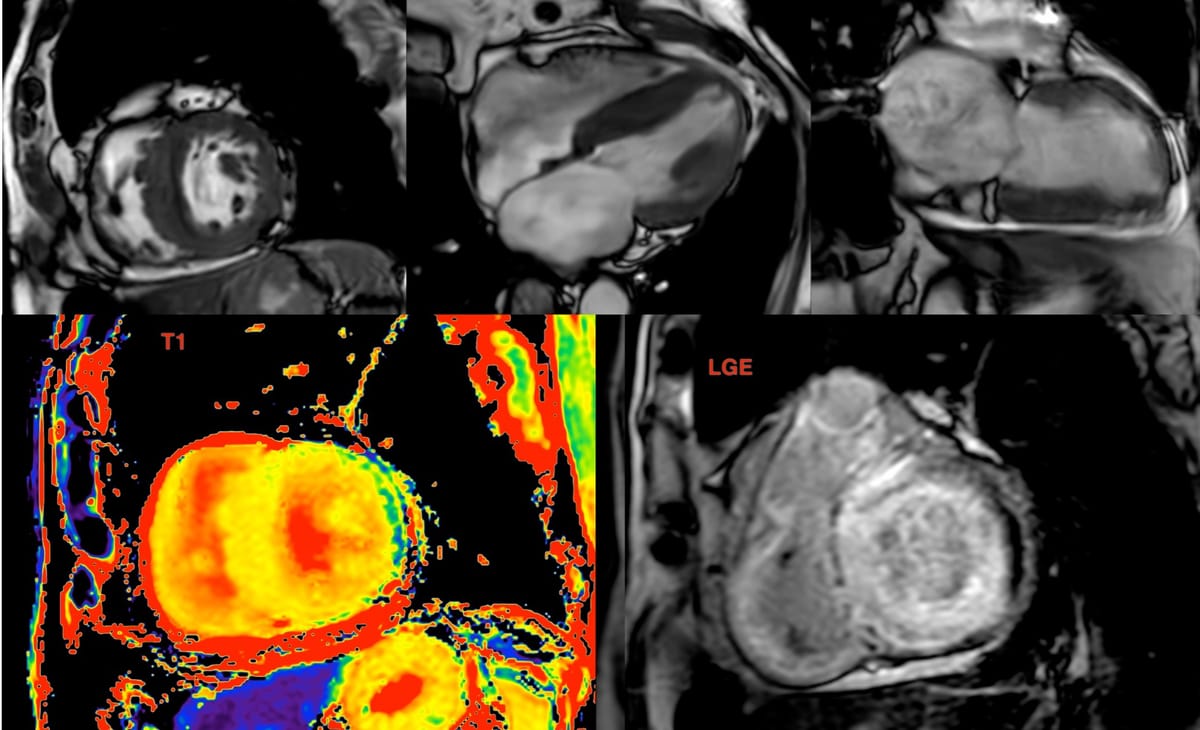

Cardiac MRI shows marked RV hypertrophy, the cause of which is abnormal musculature in the subpulmonic region, dividing the heart into a high-pressure proximal chamber and a low-pressure distal chamber, a double-chambered right ventricle or DCRV.

In this case, there are abnormal septo-parietal and septo-marginal trabeculae causing the stenosis.